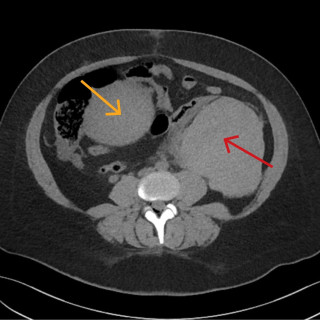

En mann i 50-årene ble innlagt etter residiverende episoder med brystsmerter. På innleggelsesdagen synkoperte han fra sittende stilling. Utredningsforløpet avdekket en diagnose som er sjelden, men med klassiske symptomer og funn. En mann i 50-årene med kjent hypertensjon, velregulert med kandesartan (tabletter, 8 mg × 1), ble henvist til akuttmottaket på grunn av episoder med brystsmerter. Han var normalvektig, hadde aldri røykt og hadde ingen rusbrukslidelse, og det var ingen kjent diabetes, hyperkolesterolemi, opphopning av hjertesykdom eller prematur hjertedød i familien. Over en periode på...